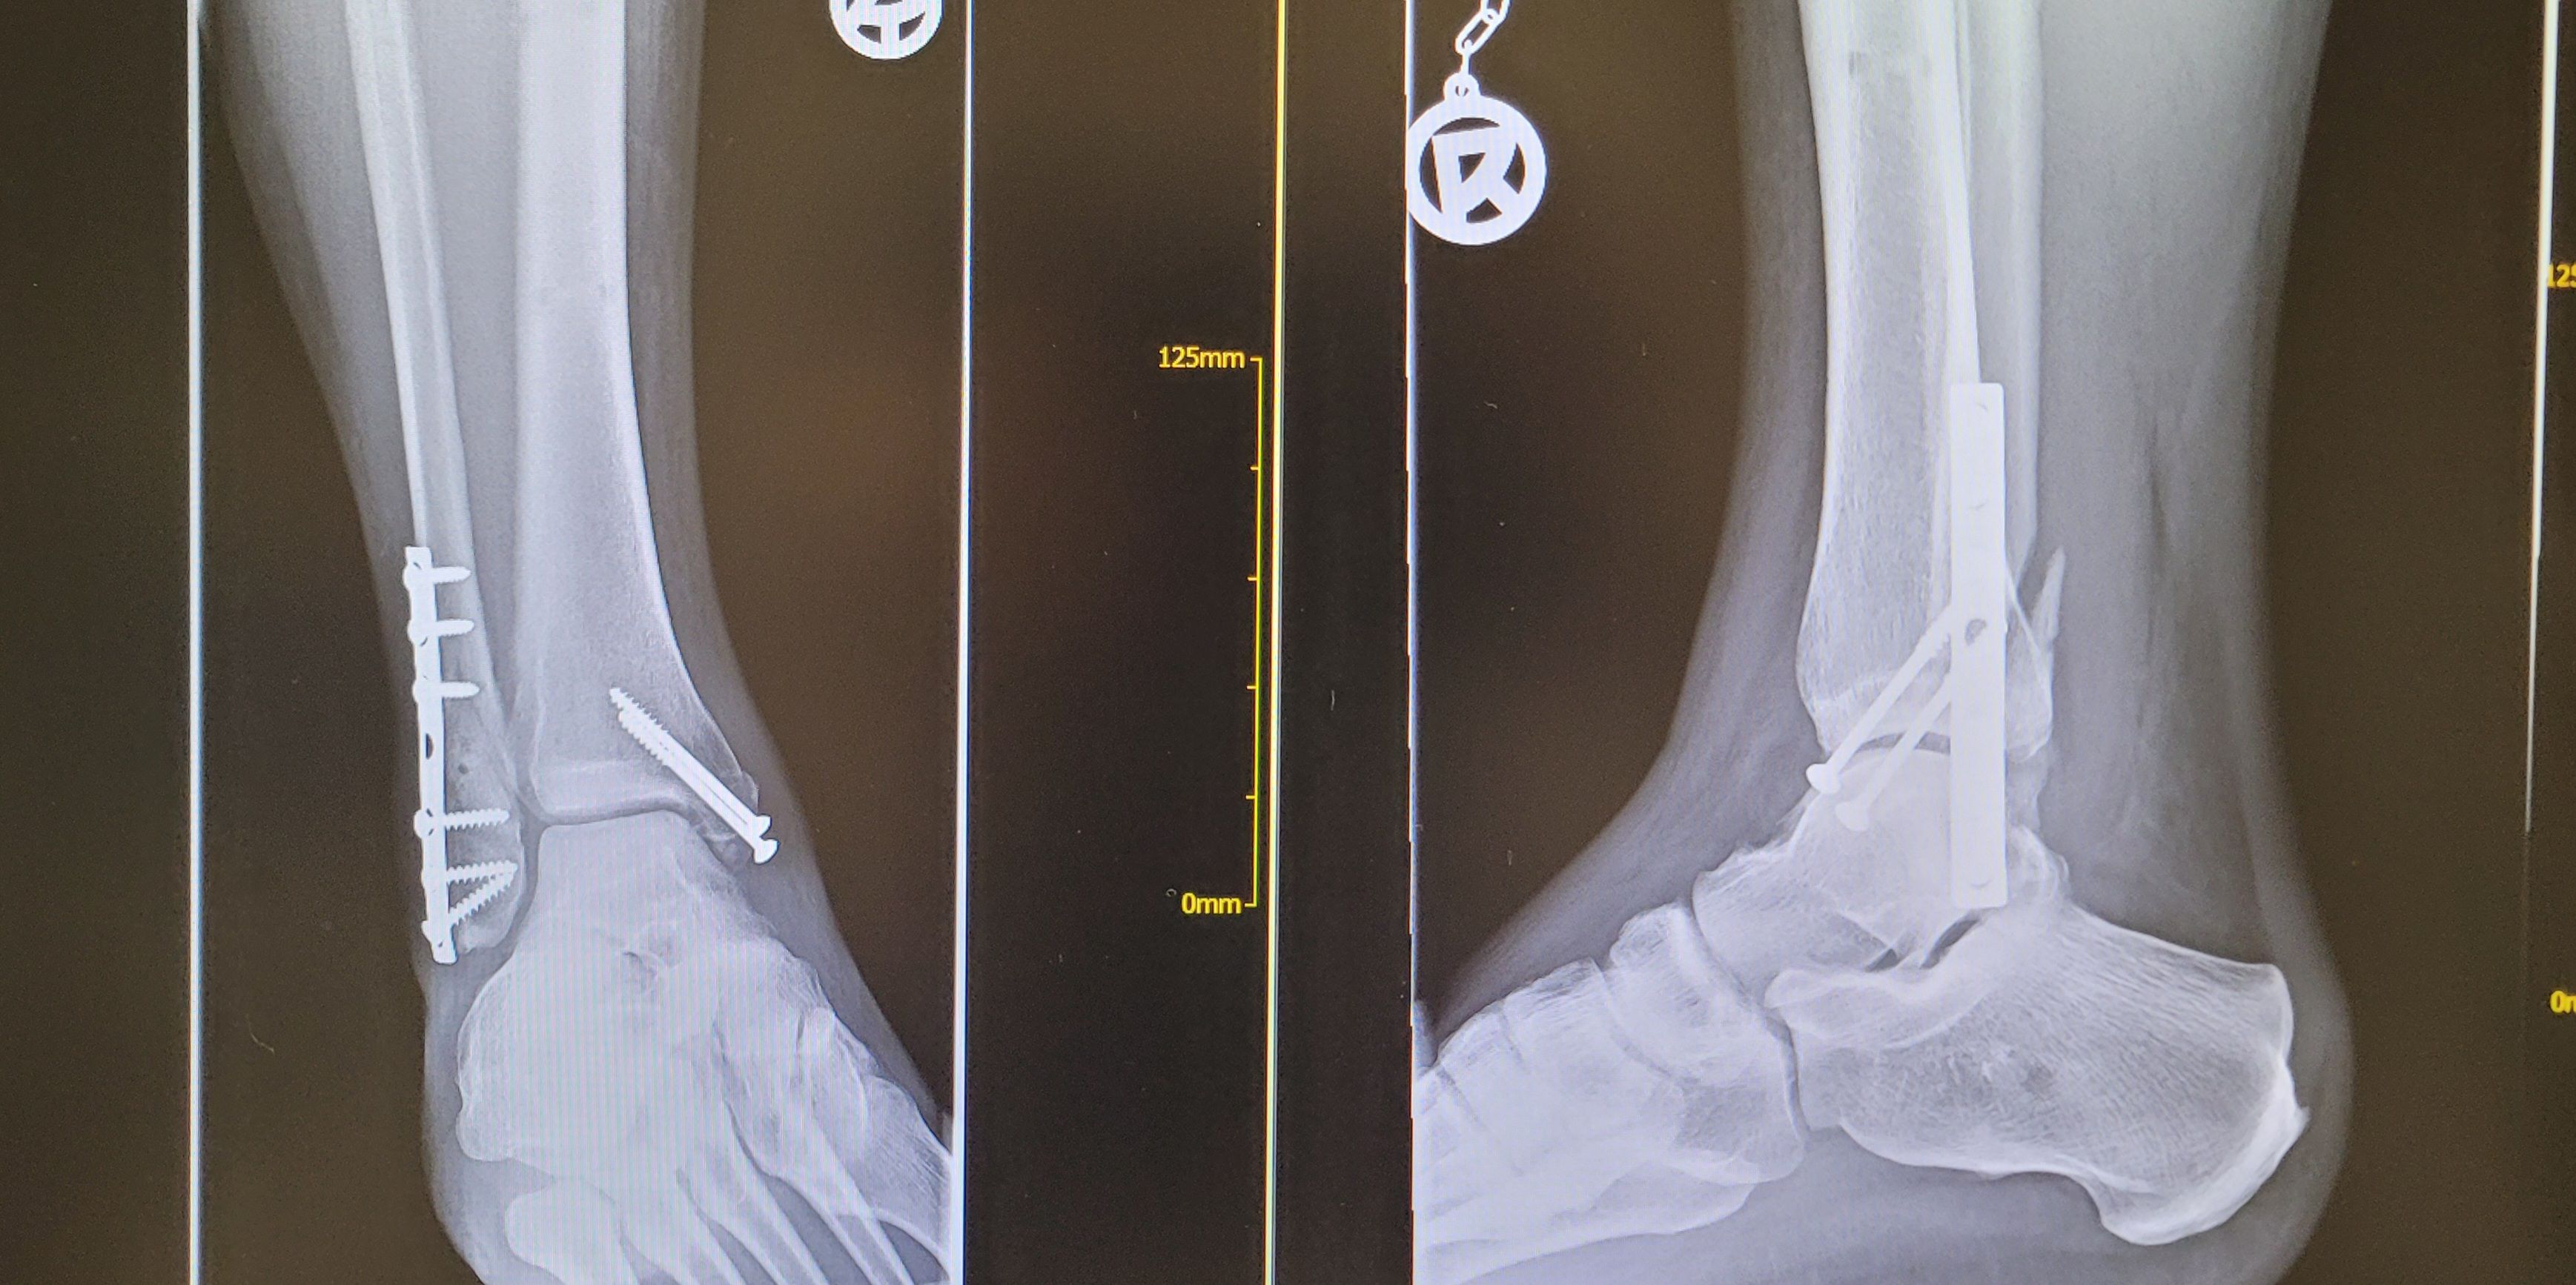

Interesse ja. Aber ich glaub ich fahr dieses Jahr nichts ambitioniertes. Verheilt nicht gut der fuss

Anhänge

• 20230209_095332.jpg

20230209_095332.jpg

1,3 MB · Aufrufe: 223

Aua! Das sieht fies aus. Ich leide aus der Ferne mit;)